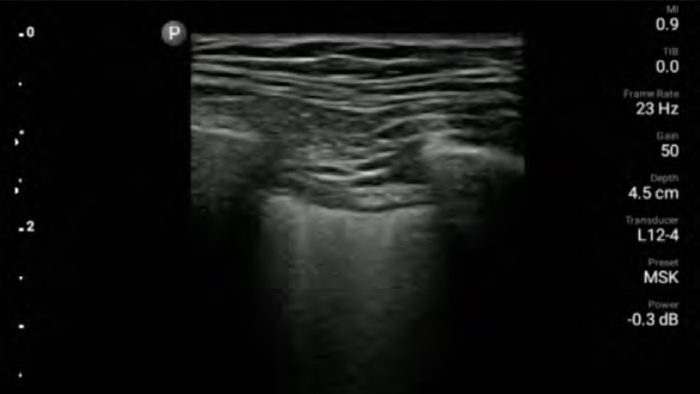

Lumify handheld ultrasound for anesthesiology helps you clearly visualize border definition with your needle placement, surrounding nerves, vessels and fascial planes.

Lumify helps you clearly visualize needle placement, surrounding nerves, vessels and fascial planes.

Lumify L12-4 broadband linear array transducer

• 12 to 4 MHz extended operating frequency range

• Aperture size: 34mm

• 2D, steerable color Doppler, M-mode, advancedXRES and multivariate harmonic imaging, SonoCT

• High resolution imaging for shallow applications: soft tissue, vascular, superficial, musculoskeletal and lung